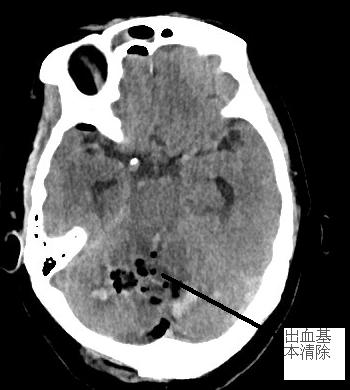

患者徐阿婆,71歲,3月13日約11時(shí)被發(fā)現(xiàn)躺于田野中,呼之不應(yīng)。家屬趕緊將其送至我院急診科。通過腦部CT掃描出小腦大量出血,出血量約30ml,小腦半球、小腦蚓、腦干(生命中樞)受壓,環(huán)池變窄,且患者處于昏迷狀態(tài),雙側(cè)瞳孔對(duì)光反射遲鈍,情況危急。為搶救生命,需要進(jìn)行開顱手術(shù)治療。我院神經(jīng)外科醫(yī)生謝志芳告知家屬病情后,家屬考慮到徐阿婆年紀(jì)較大、經(jīng)濟(jì)狀況不佳等情況,對(duì)是否進(jìn)行手術(shù)猶豫不決。

我院神經(jīng)外科在做好積極術(shù)前準(zhǔn)備的同時(shí),聯(lián)系福醫(yī)大附二院神經(jīng)外科當(dāng)值專家。專家到位后立即將患者送入手術(shù)室。術(shù)中見小腦膨脹明顯,壓力高,予充分清除血腫后,腦組織壓力減低,腦血管搏動(dòng)有力。術(shù)后,患者生命征平穩(wěn)。

左圖為術(shù)前顱內(nèi)血腫,右圖為術(shù)后原血腫位置。

復(fù)查CT后,徐阿婆小腦內(nèi)血腫基本清除,壓力下降。后續(xù)在我院神經(jīng)外科與福醫(yī)大附二院神經(jīng)外科專家聯(lián)合治療下,病情好轉(zhuǎn),4月12日痊愈出院。